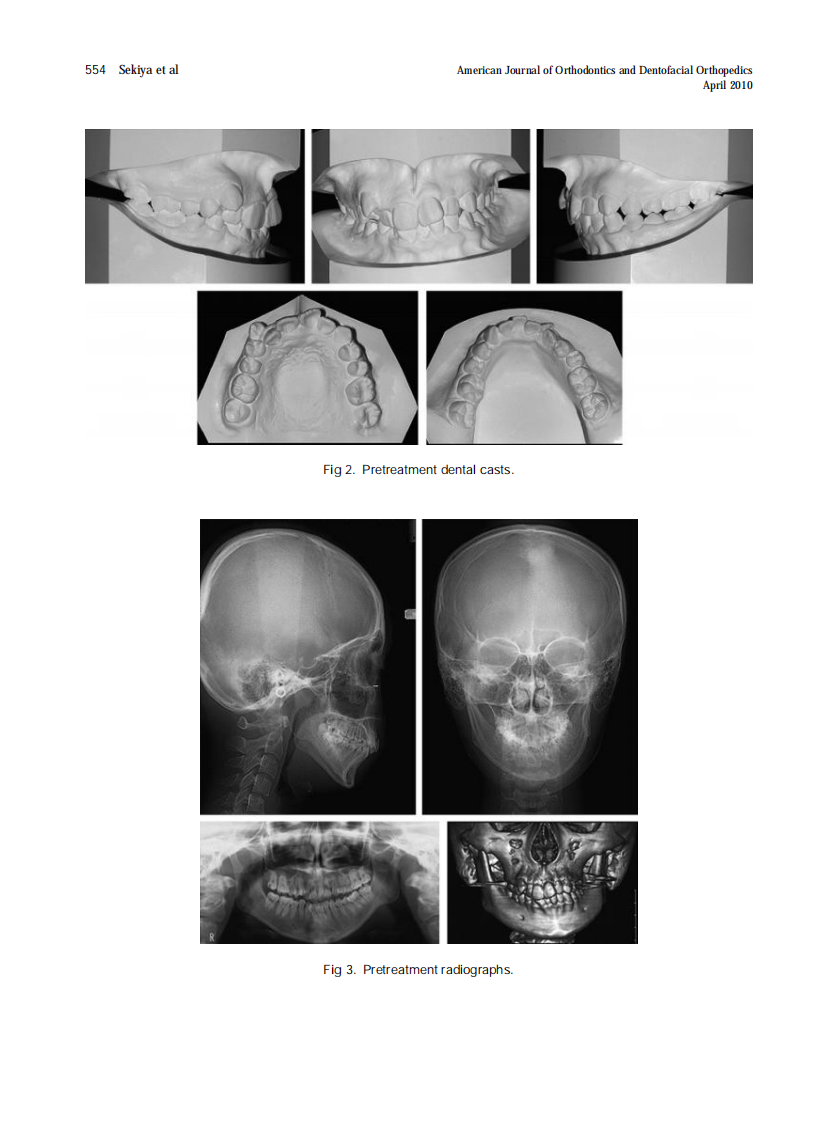

AJO-DO

2010_137_4_552_562.pdf